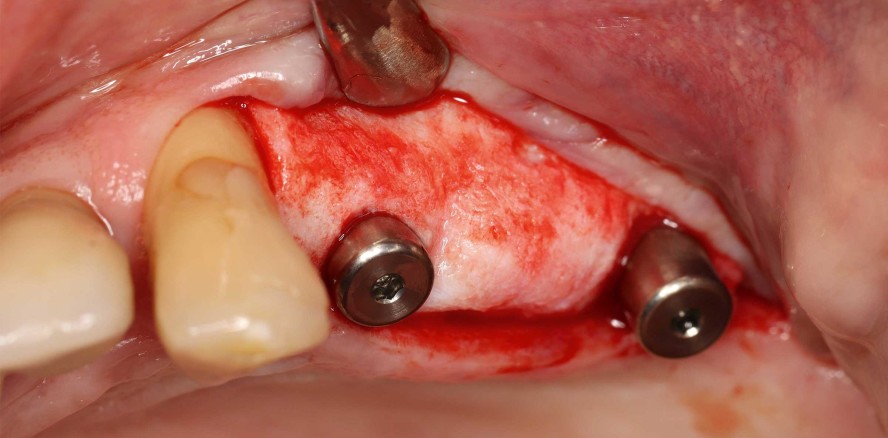

Der Reentry erfolgte sechs Monate nach Knochenaufbau. Nach Bildung eines Mukoperiostlappens zeigte sich ein hervorragend konsolidierter Kieferkamm ohne Zeichen einer Graft-Resorption. Das Volumen war bis zu den Schraubenköpfen komplett erhalten (Abb. 11). Die Schrauben ließen sich problemlos entfernen und die Insertion von zwei Implantaten (Screw-Line [ 4,3, L11; Camlog) war aufgrund des ausreichenden Knochenangebots in korrekter Position möglich (Abb. 12–14). Abbildung 14 zeigt das Röntgenbild nach Implantation und Abbildung 15 den spannungsfreien Wundverschluss, bei welchem auf vertikale Entlastungen verzichtet wurde. Im Rahmen der Freilegung sollten Maßnahmen ergriffen werden, um das Weichgewebsdefizit auszugleichen (Abb. 16). Hierbei wurde eine azelluläre dermale Matrix (Novomatrix) angewendet, um sowohl die Breite als auch die Höhe des Weichgewebes zu optimieren. Darüber hinaus wurde die rekonstruktive Gewebematrix mit Hyaluronsäure benetzt. Im Anschluss wurden zwei Gingivaformer inseriert, das Operationsgebiet durch einen spannungsfreien Wundverschluss verschlossen und Hyaluronsäure zur verbesserten Wundheilung adaptiert (Abb. 17 und 18). Der Heilungsverlauf wie auch die weitere Versorgung gestalteten sich unauffällig. Abbildung 19 zeigt die optimierten Weichgewebsverhältnisse. Abbildung 20 und 21 zeigen die klinische Situation nach Einsetzen der finalen Arbeit mit abschließendem Röntgenbild (Abb. 21).